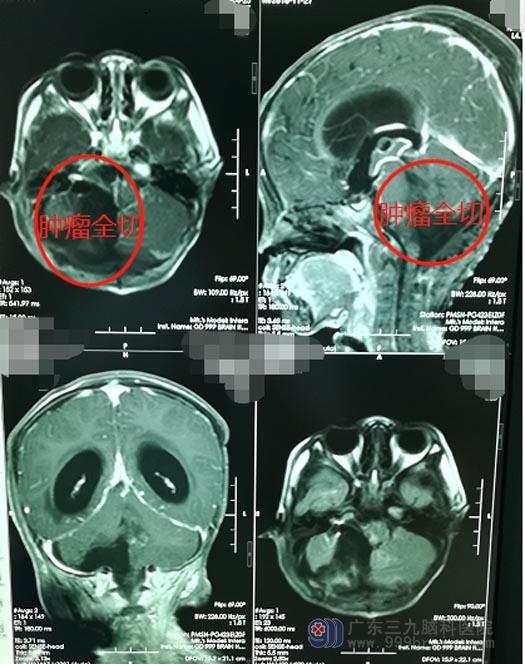

入住神经外五科后,主管医生李兴可立即为鹏鹏安排了一系列的专科检查,诊断结果为:脑干、四脑室、双侧小脑半球占位。

肿瘤所在的位置有丰富的血管和神经,此区域被称为手术禁区,稍有不慎,会损伤脑干、血管及神经,出现严重的并发症。但孩子病情非常危急,需要尽快手术,取得家属同意之后,由鲁明主刀在全麻下行“脑干、四脑室、双侧小脑半球肿瘤切除术+气管切开术”,术中见肿瘤侵蚀四脑室、双侧小脑半球、脑干,脑干已被肿瘤挤压至左侧,右侧三叉神经、面神经、后组颅神经均被肿瘤包裹;在显微镜下小心翼翼地将肿瘤全部切除,神经、血管均未受损伤。

术后第三天,鹏鹏生命体征平稳,已经能够自主活动,目前正继续术后的康复治疗。